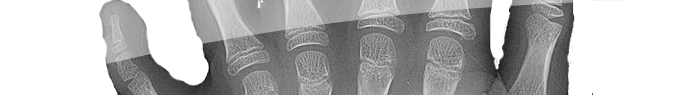

Du grec poly plusieurs et dactyle doigts, la polydactylie n'est pas, comme vous pouvez le croire au premier abord, un ancien cousin du Pterodactylus mais désigne la présence d'un nombre de doigts supérieur à la normale.